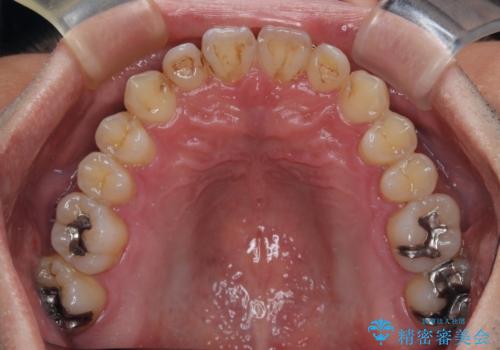

内側に引っ込んだ歯を治したい インビザラインの矯正治療

- 前歯のデコボコとクロスバイトを治したいとのことで来院された患者様です。

上下顎ともに歯列全体の側方拡大とIPR(歯と歯の間を削る)によってデコボコとクロスバイトが解消するように設計し、インビザラインにより治療を行うこととしました。

反対咬合特有の治療途中の前歯の干渉が長く続き、治療中に食事をとりにくく、ご迷惑をおかけしました。

前歯の咬み合わせの調整などを行い、安定した咬み合わせに仕上げることができました。